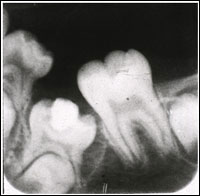

乳臼歯の骨性癒着による咬合異常

4. 下顎左側第一大臼歯の著しい近心傾斜

5. 下顎左側第二乳臼歯の埋伏低位と後継永久歯胚の位置異常

2. 低位乳臼歯の自然萌出なければ下顎第二乳臼歯の抜歯